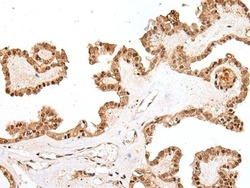

- Main image

- Experimental details

- Immunohistochemical analysis of PTOV1 in paraffin-embedded Human thyroid cancer tissue using (left) PTOV1 Polyclonal Antibody (Product # PA5-67569) at a 1:25 dilution and (right) is treated with synthetic peptide. (Original magnification: x200).